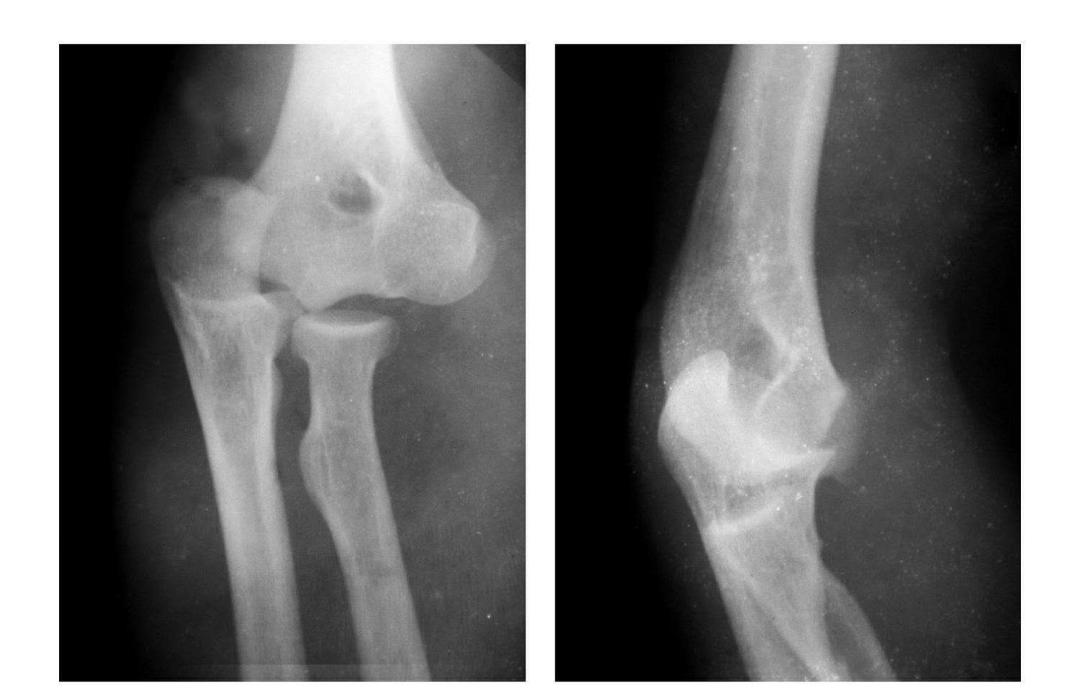

肱骨小头骨骺滑脱

例:肱骨小头骨骺向外移位并呈倾斜状。

肱骨下端双髁骨折

例1:肱骨内髁及外髁骨折,该两髁骨块均呈向内、外翻转移位。

例2:肱骨内上髁Ⅲ度骨折并外上髁撕脱骨折。

例3:肱骨内上髁Ⅳ度骨折并外上髁撕脱骨折。